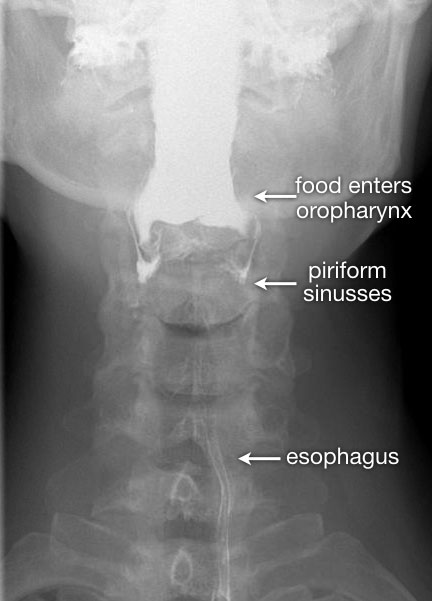

Tư thế thẳng (AP-view) quan trọng để đánh giá sự bất đối xứng.

Sau khi hoàn thành chuỗi hình ảnh giai đoạn hầu họng, cần theo dõi bolus thuốc cản quang toàn bộ đường đi xuống đến chỗ nối thực quản-dạ dày.